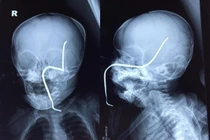

Tại BV, sau khi thăm khám, chụp X-quang, các bác sĩ xác định bệnh nhân bị khuyết sọ vùng đỉnh phải và chỉ định phẫu thuật. Tuy nhiên, do tình trạng trạng của bệnh nhân chưa ổn định nên ca phẫu thuật chưa thực hiện được. Hiện tại, bệnh nhân tiếp tục được chăm sóc, điều trị tại BV.